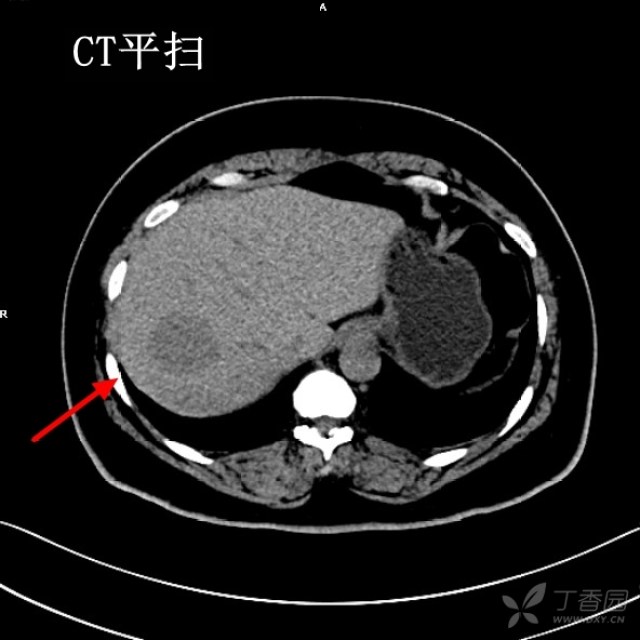

入院时,ct示右肝前叶原发性肝癌(hcc),向包膜外突出.大小42*38mm.

查体 辅查 查体,上腹部压痛明显,肝脏肋下5厘米, 腹部ct如下.

小肝癌